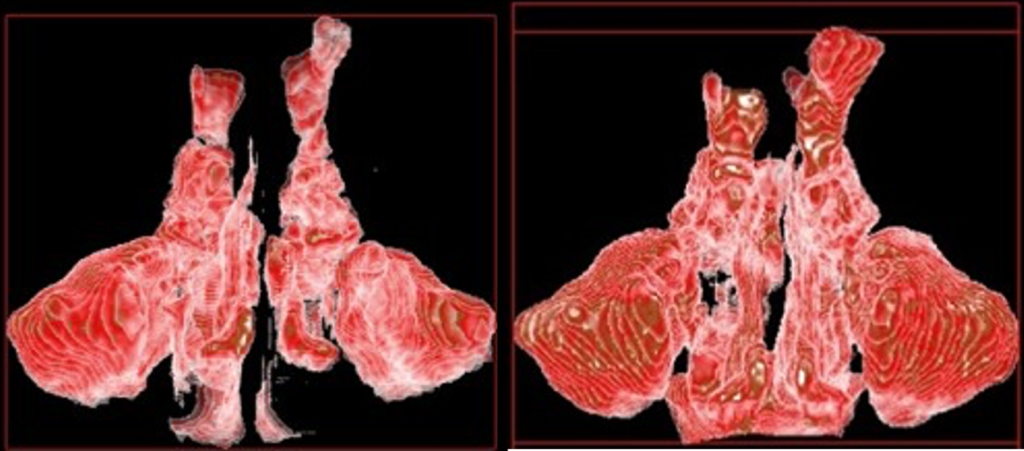

上下顎の劣成長は、空気の通り道である、気道や鼻腔を狭くしてしまいます。明確な症状として表出するかどうかには個人差もありますが、自覚症状の有無に関わらず、大多数の子どもたちは、常に酸素不足のリスクに晒されています。

治療によって、上顎が上がれば、下顎も連動して上がり、気道の圧迫から開放されます。そして舌の位置も上がり、上顎につきやすくなります。基本的に上顎の位置が上がり、骨格のゆがみが改善され、舌が上顎につくようになれば、歯とは自然と並びます。

耳鼻科とも連携し、気道や鼻腔の通気性、歯並び、骨格の変化を総合的に診査しながら、当院のランパセラピーはゴールへと向かいます。